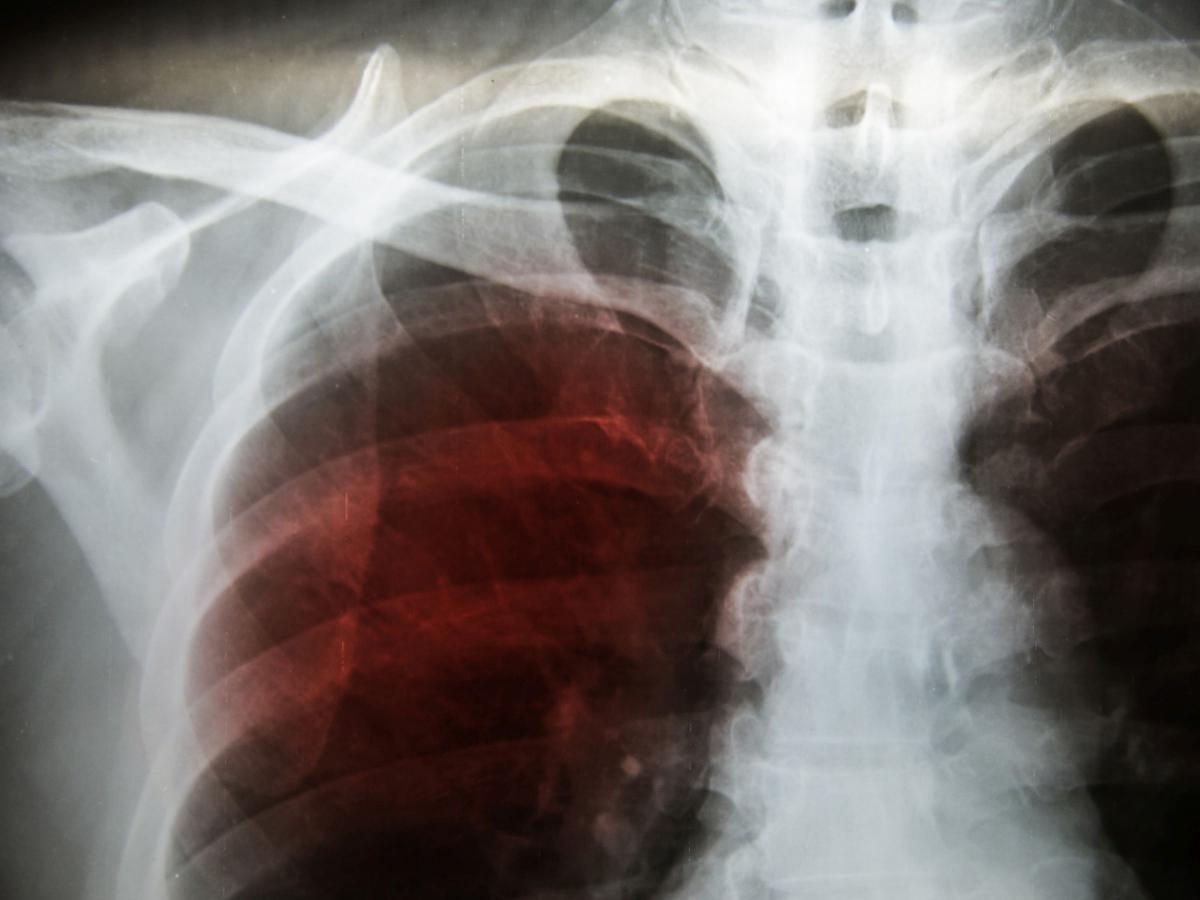

La principale minaccia per la salute associata all'amianto è l'inalazione delle sue fibre. Una volta inalate, queste fibre possono rimanere intrappolate nei polmoni per molti anni, causando infiammazioni, cicatrici e, a lungo termine, gravi malattie come l'asbestosi, il mesotelioma e altri tipi di cancro ai polmoni.

Il mesotelioma pleurico, una delle malattie più devastanti legate all'amianto, ha un periodo di latenza estremamente lungo, che può variare dai 20 ai 50 anni. Ciò significa che le persone che hanno subito l'esposizione molti anni fa possono manifestare i sintomi della malattia solo ora. Questa lunga latenza rende difficile il monitoraggio e la diagnosi precoce, contribuendo alla gravità dell'epidemia di mesotelioma.